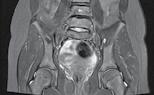

Figura 3: Bărbat de 69 de ani cu metastaze avansate la nivelul femurului proximal și sacrumului. Imaginea arată osteoliză semnificativă, indicând riscul iminent de fractură patologică. (A) Prezintă o tu-

moră osteolitică în femur, iar B și C arată scanări CT care evidențiază extinderea metastazelor în femur și sacrum. Scintigrafia osoasă (D) oferă dovezi suplimentare ale răspândirii extinse a bolii. Din cauza prezenței unei tumori inoperabile, pacientul a urmat un plan de tratament pentru ameliorarea simptomelor și îmbunătățirea calității vieții, care a inclus radioterapie și ablație cu radiofrecvență pentru reducerea durerii și stabilizarea osului.